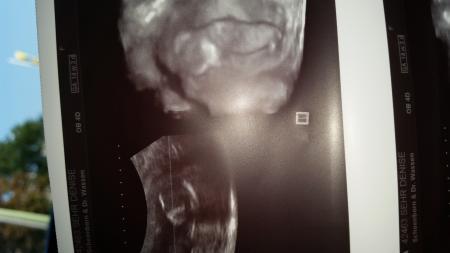

Hi Hatte heute meinen Termin und bisher sah alles okay aber bis zur Feindiagnostik habe ich schon noch Ängste da ich selber eine LkG habe . Naja das Geschlecht wollte es noch nicht zeigen aber ich glaube ,dass es ein Junge ist :-) Wünsche euch allen einen schönen Tag